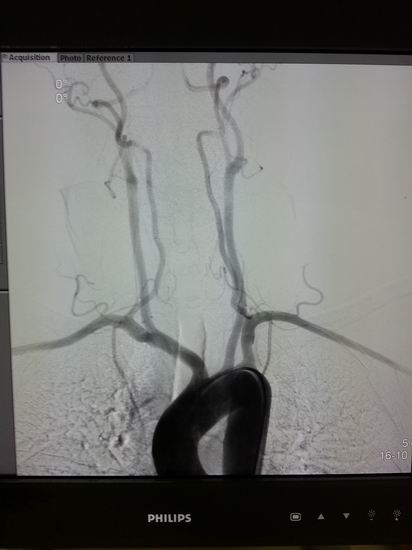

高档数字减影、血管造影系统 Allura Xper FD20

名称:高档数字减影、血管造影系统 Allura Xper FD20

主要功能:采用大平板科技,结合2K影像链,提供极佳图像细节解析能力,1250mA成像能力与“透心凉”高散热球管,“Refresh light”技术消除动态采集时的鬼影,图像质量更高。